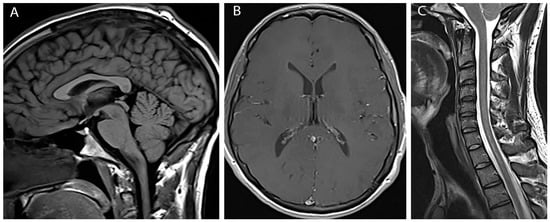

The patient continues to have improvement of bilateral hand strength. His headaches, neck, and back pain all resolved over the following month. Repeat imaging performed approximately three months following the fifth and final therapeutic blood patch showed complete resolution of pachymeningeal enhancement, tonsillar herniation and cord edema with only a tiny residual syrinx (Figure 3).

Figure 3. Post-treatment images (A) Sagittal T1 weighted image shows resolution of tonsillar herniation; (B) Axial post gadolinium image shows resolution of pachymengeal enhancement; (C) Sagittal T2 weighted image shows resolution of cord edema and syrinx.